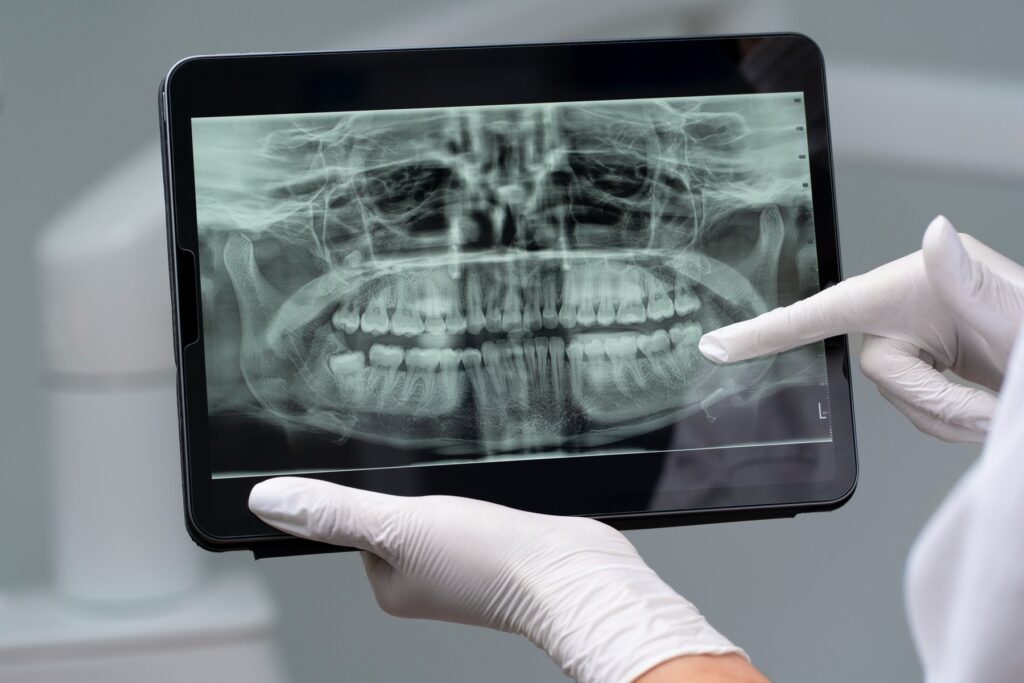

Badania pantomograficzne (OPG):

Zdjęcie przedstawia stomatologa wskazującego na zdjęcie rentgenowskie zębów na tablecie w gabinecie stomatologicznym.

Zdjęcia panoramiczne standardowe: Pantomogram całego uzębienia (szczęka + żuchwa), pantomogram dzieci i młodzieży (mniejsze pole), pantomogram seniorów (ocena resztkowego uzębienia)

Pantomogram diagnostyczny przed: leczeniem ortodontycznym, ekstrakcją ósemek (zębów mądrości), planowaniem implantów, leczeniem periodontologicznym, protezowaniem